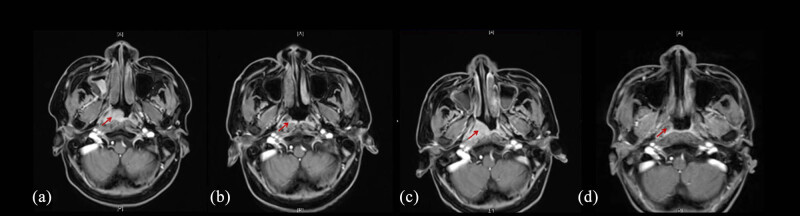

严重再生障碍性贫血(SAA)和鼻咽癌(NPC)是两种不同的疾病,如果不及时治疗,将危及生命。SAA和NPC同时发生是罕见的,并且呈现出一个复杂的治疗悖论。本研究报告了一个诊断为SAA和NPC的独特病例。患者最初接受单倍体造血干细胞移植(HSCT)以实现血液系统快速恢复,随后接受尼莫单抗+放疗治疗癌症。该病例提示,序贯单倍体HSCT和放疗可能是同时存在SAA和NPC患者的一种有希望的治疗策略。

Severe aplastic anemia (SAA) and nasopharyngeal carcinoma (NPC) are two different diseases and are life-threatening if left untreated. The co-occurrence of SAA and NPC is rare and presents a complex therapeutic paradox. This study reports a unique case of a patient diagnosed with both SAA and NPC. The patient initially underwent haploidentical hematopoietic stem cell transplantation (HSCT) to achieve rapid hematologic recovery, followed by nimotuzumab + radiotherapy for carcinoma treatment. This case suggests that sequential haploidentical HSCT and radiotherapy may represent a promising therapeutic strategy for patients with coexisting SAA and NPC.